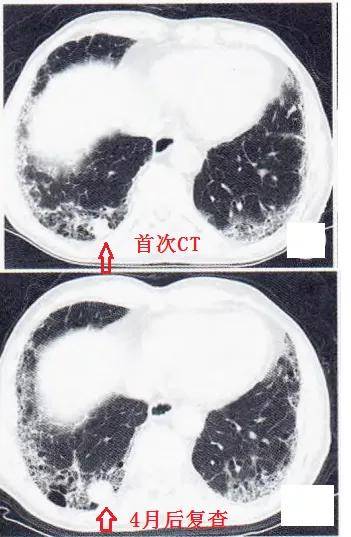

新型冠状病毒肺炎炎症后肺纤维化的现状与思考

肺纤维化图片对比

肺纤维化在ct表现图片

肺纤维化的ct图片